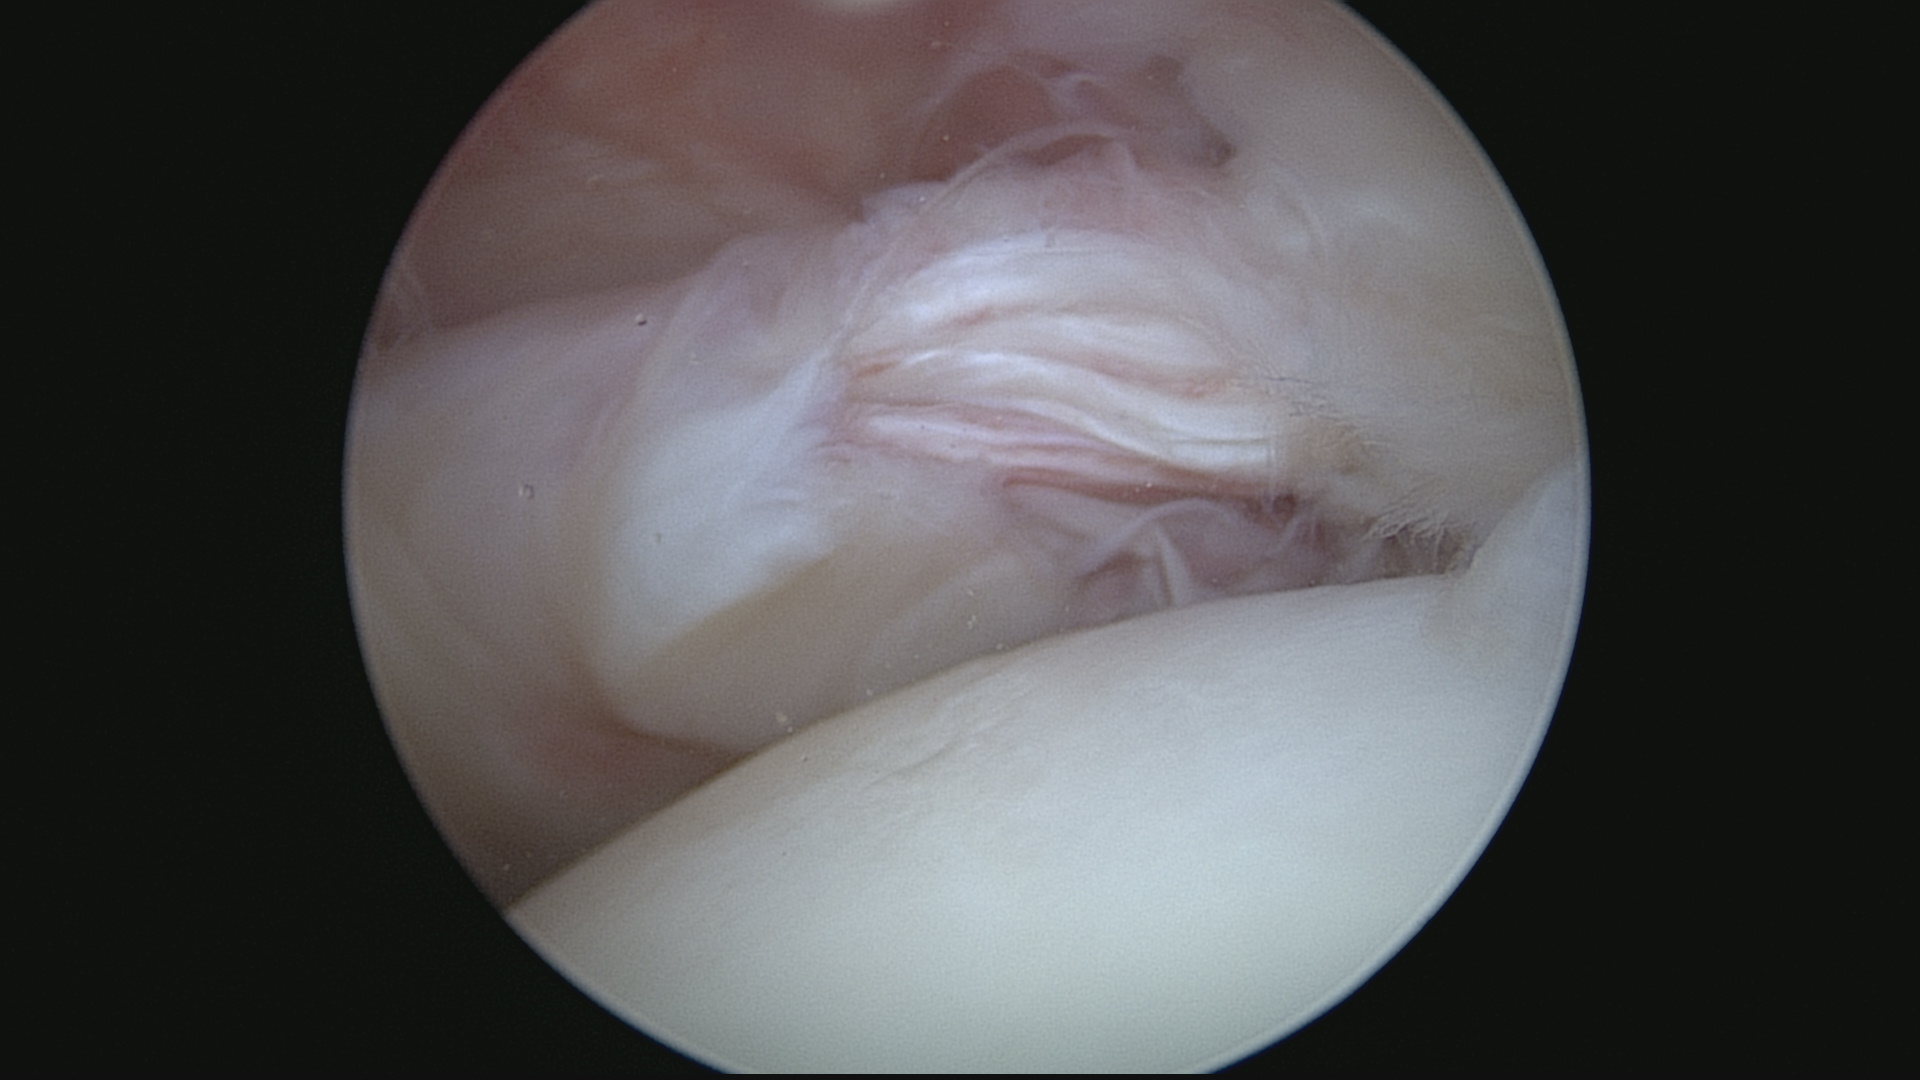

Lésion subscapularis (Vue extraarticulaire)

Réinsertion subscapularis (Vue endoarticulaire)